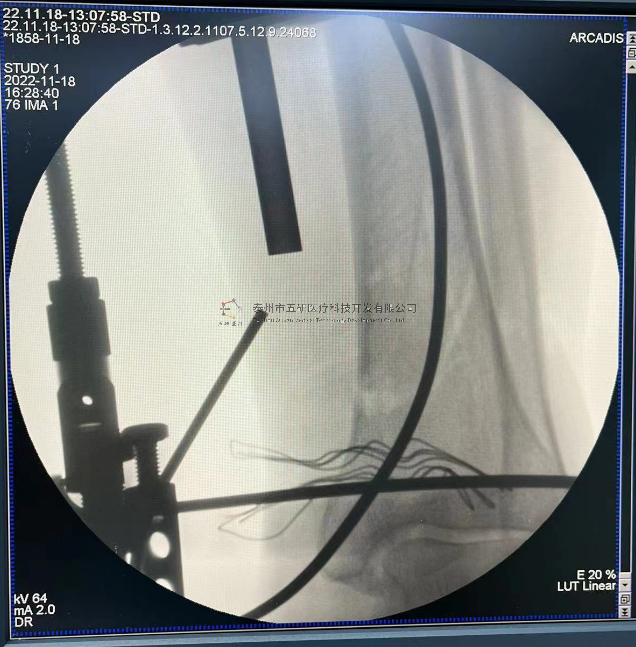

本病例踝關(guān)節(jié)骨折。手術(shù)名稱:左踝關(guān)節(jié)骨折外固定支架手術(shù)

【治療后影像】

6.png

7.png